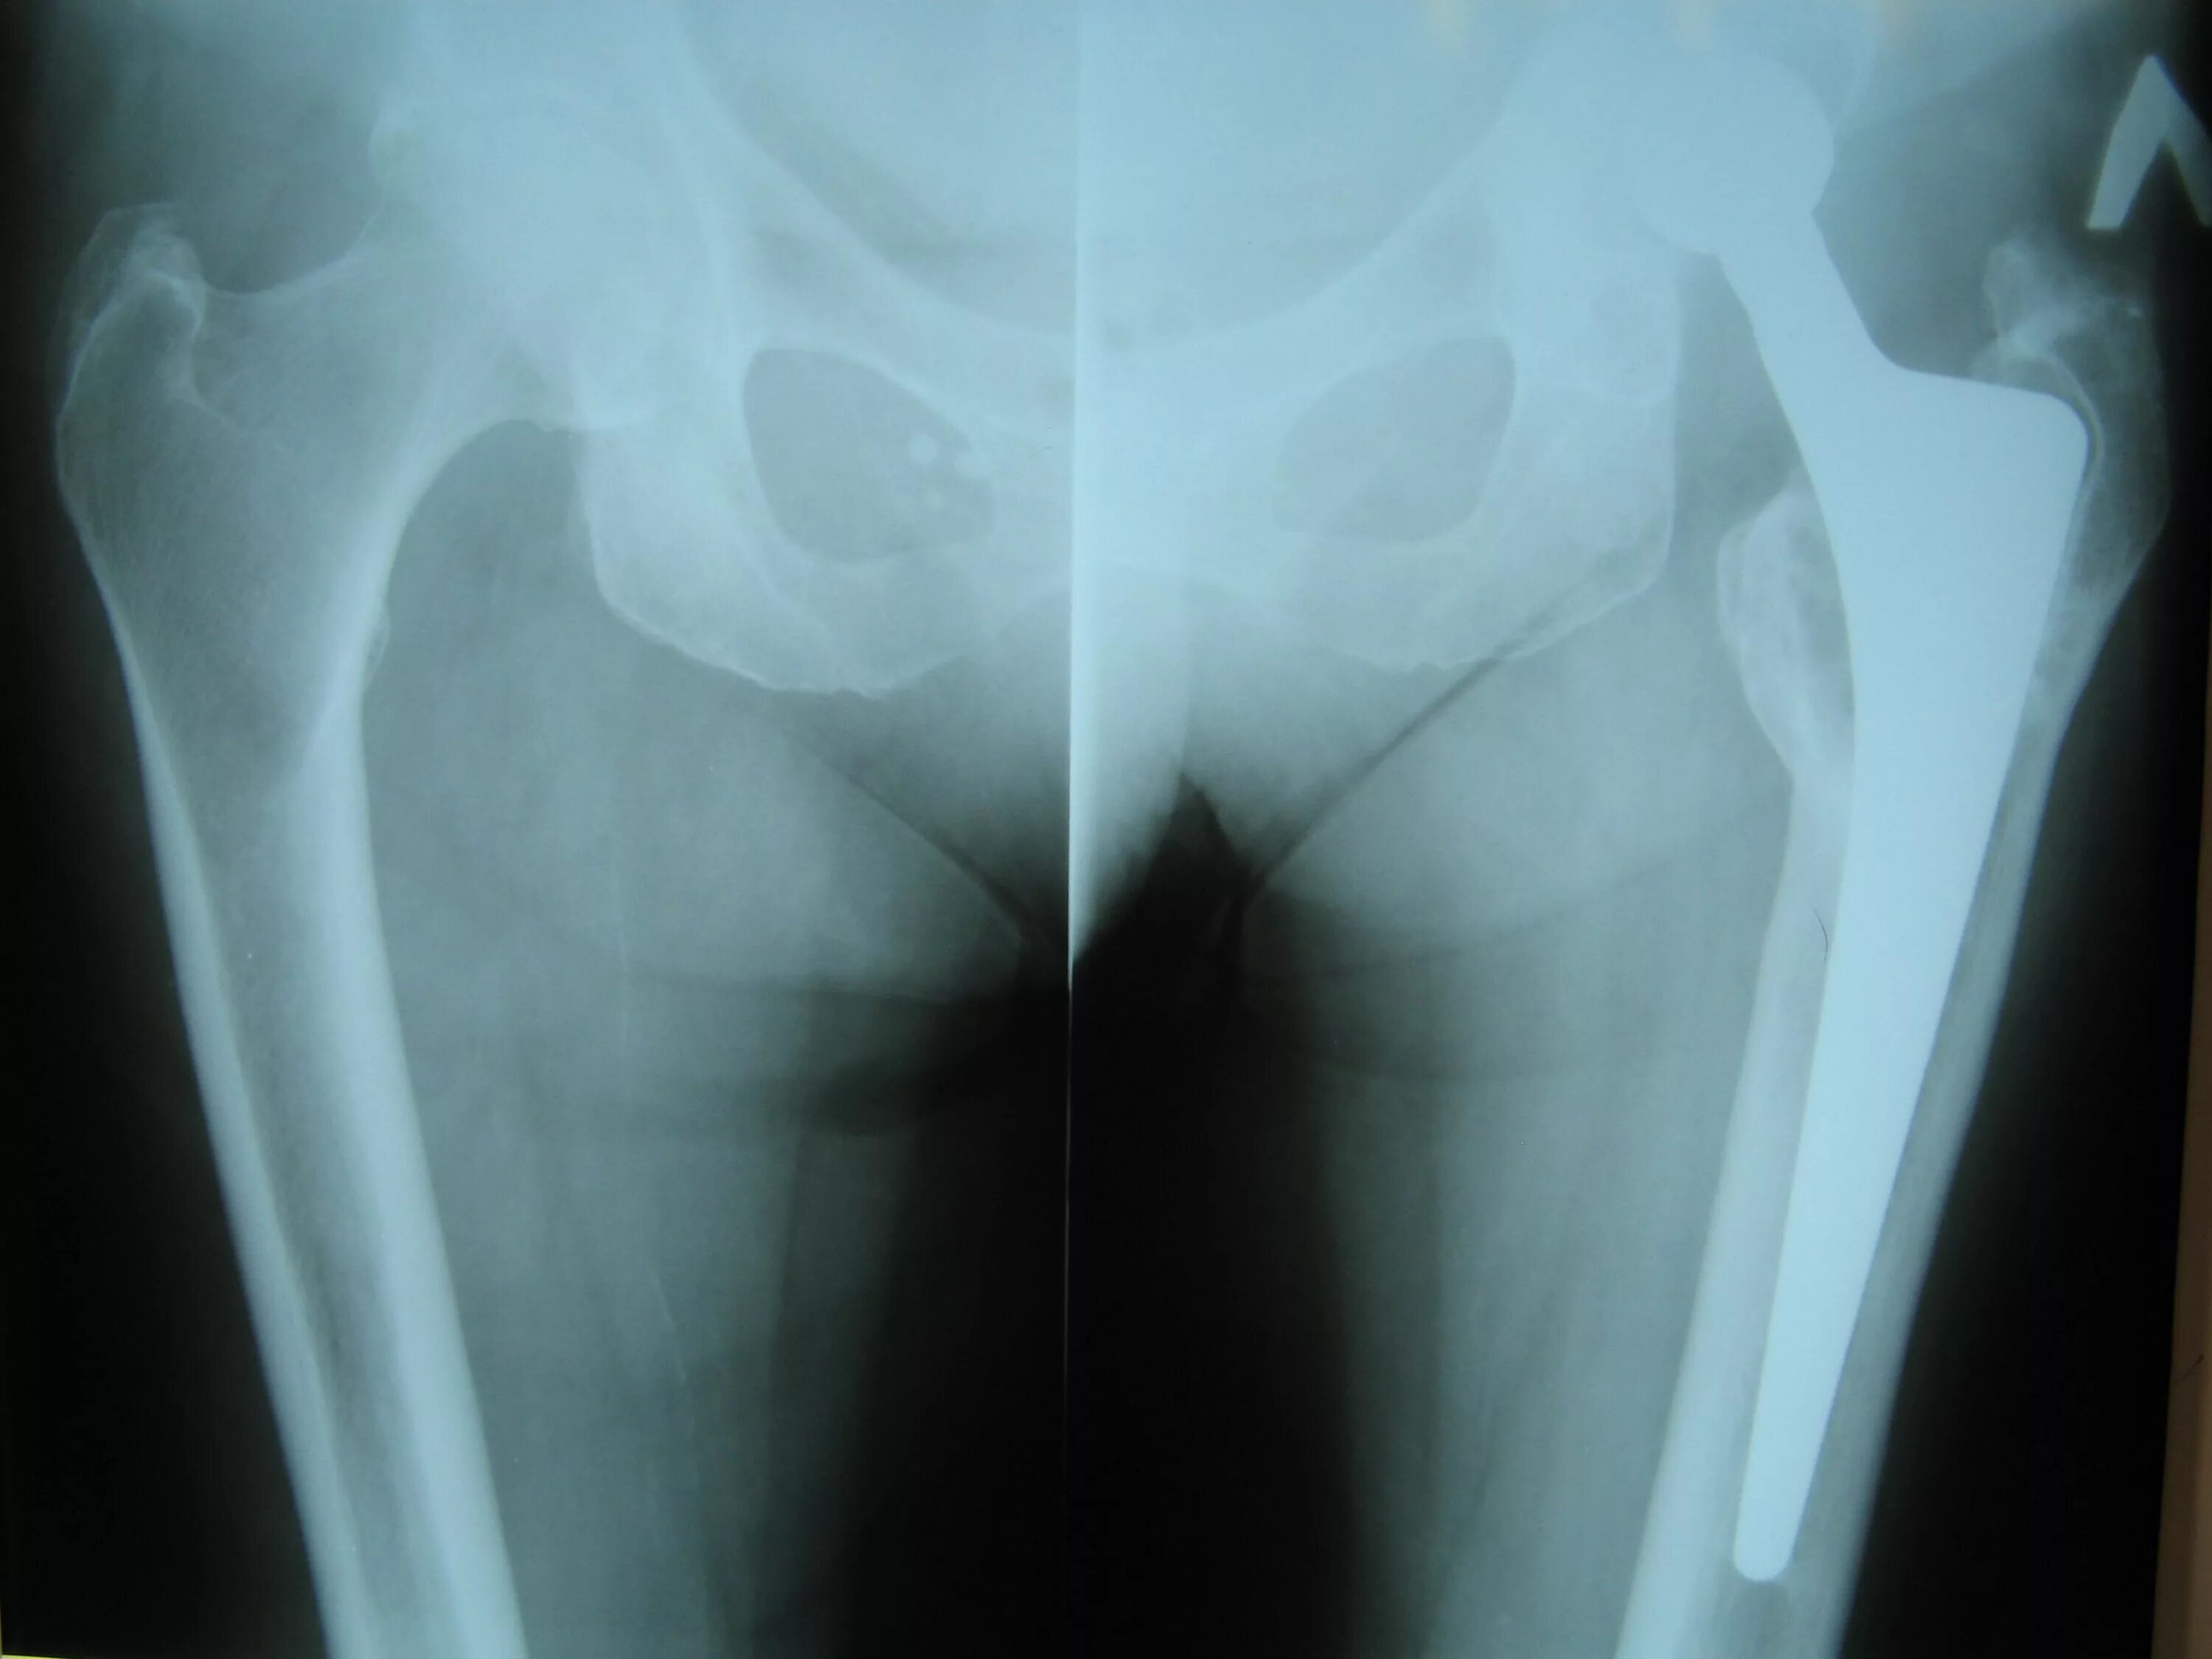

Нестабильность тазобедренного сустава